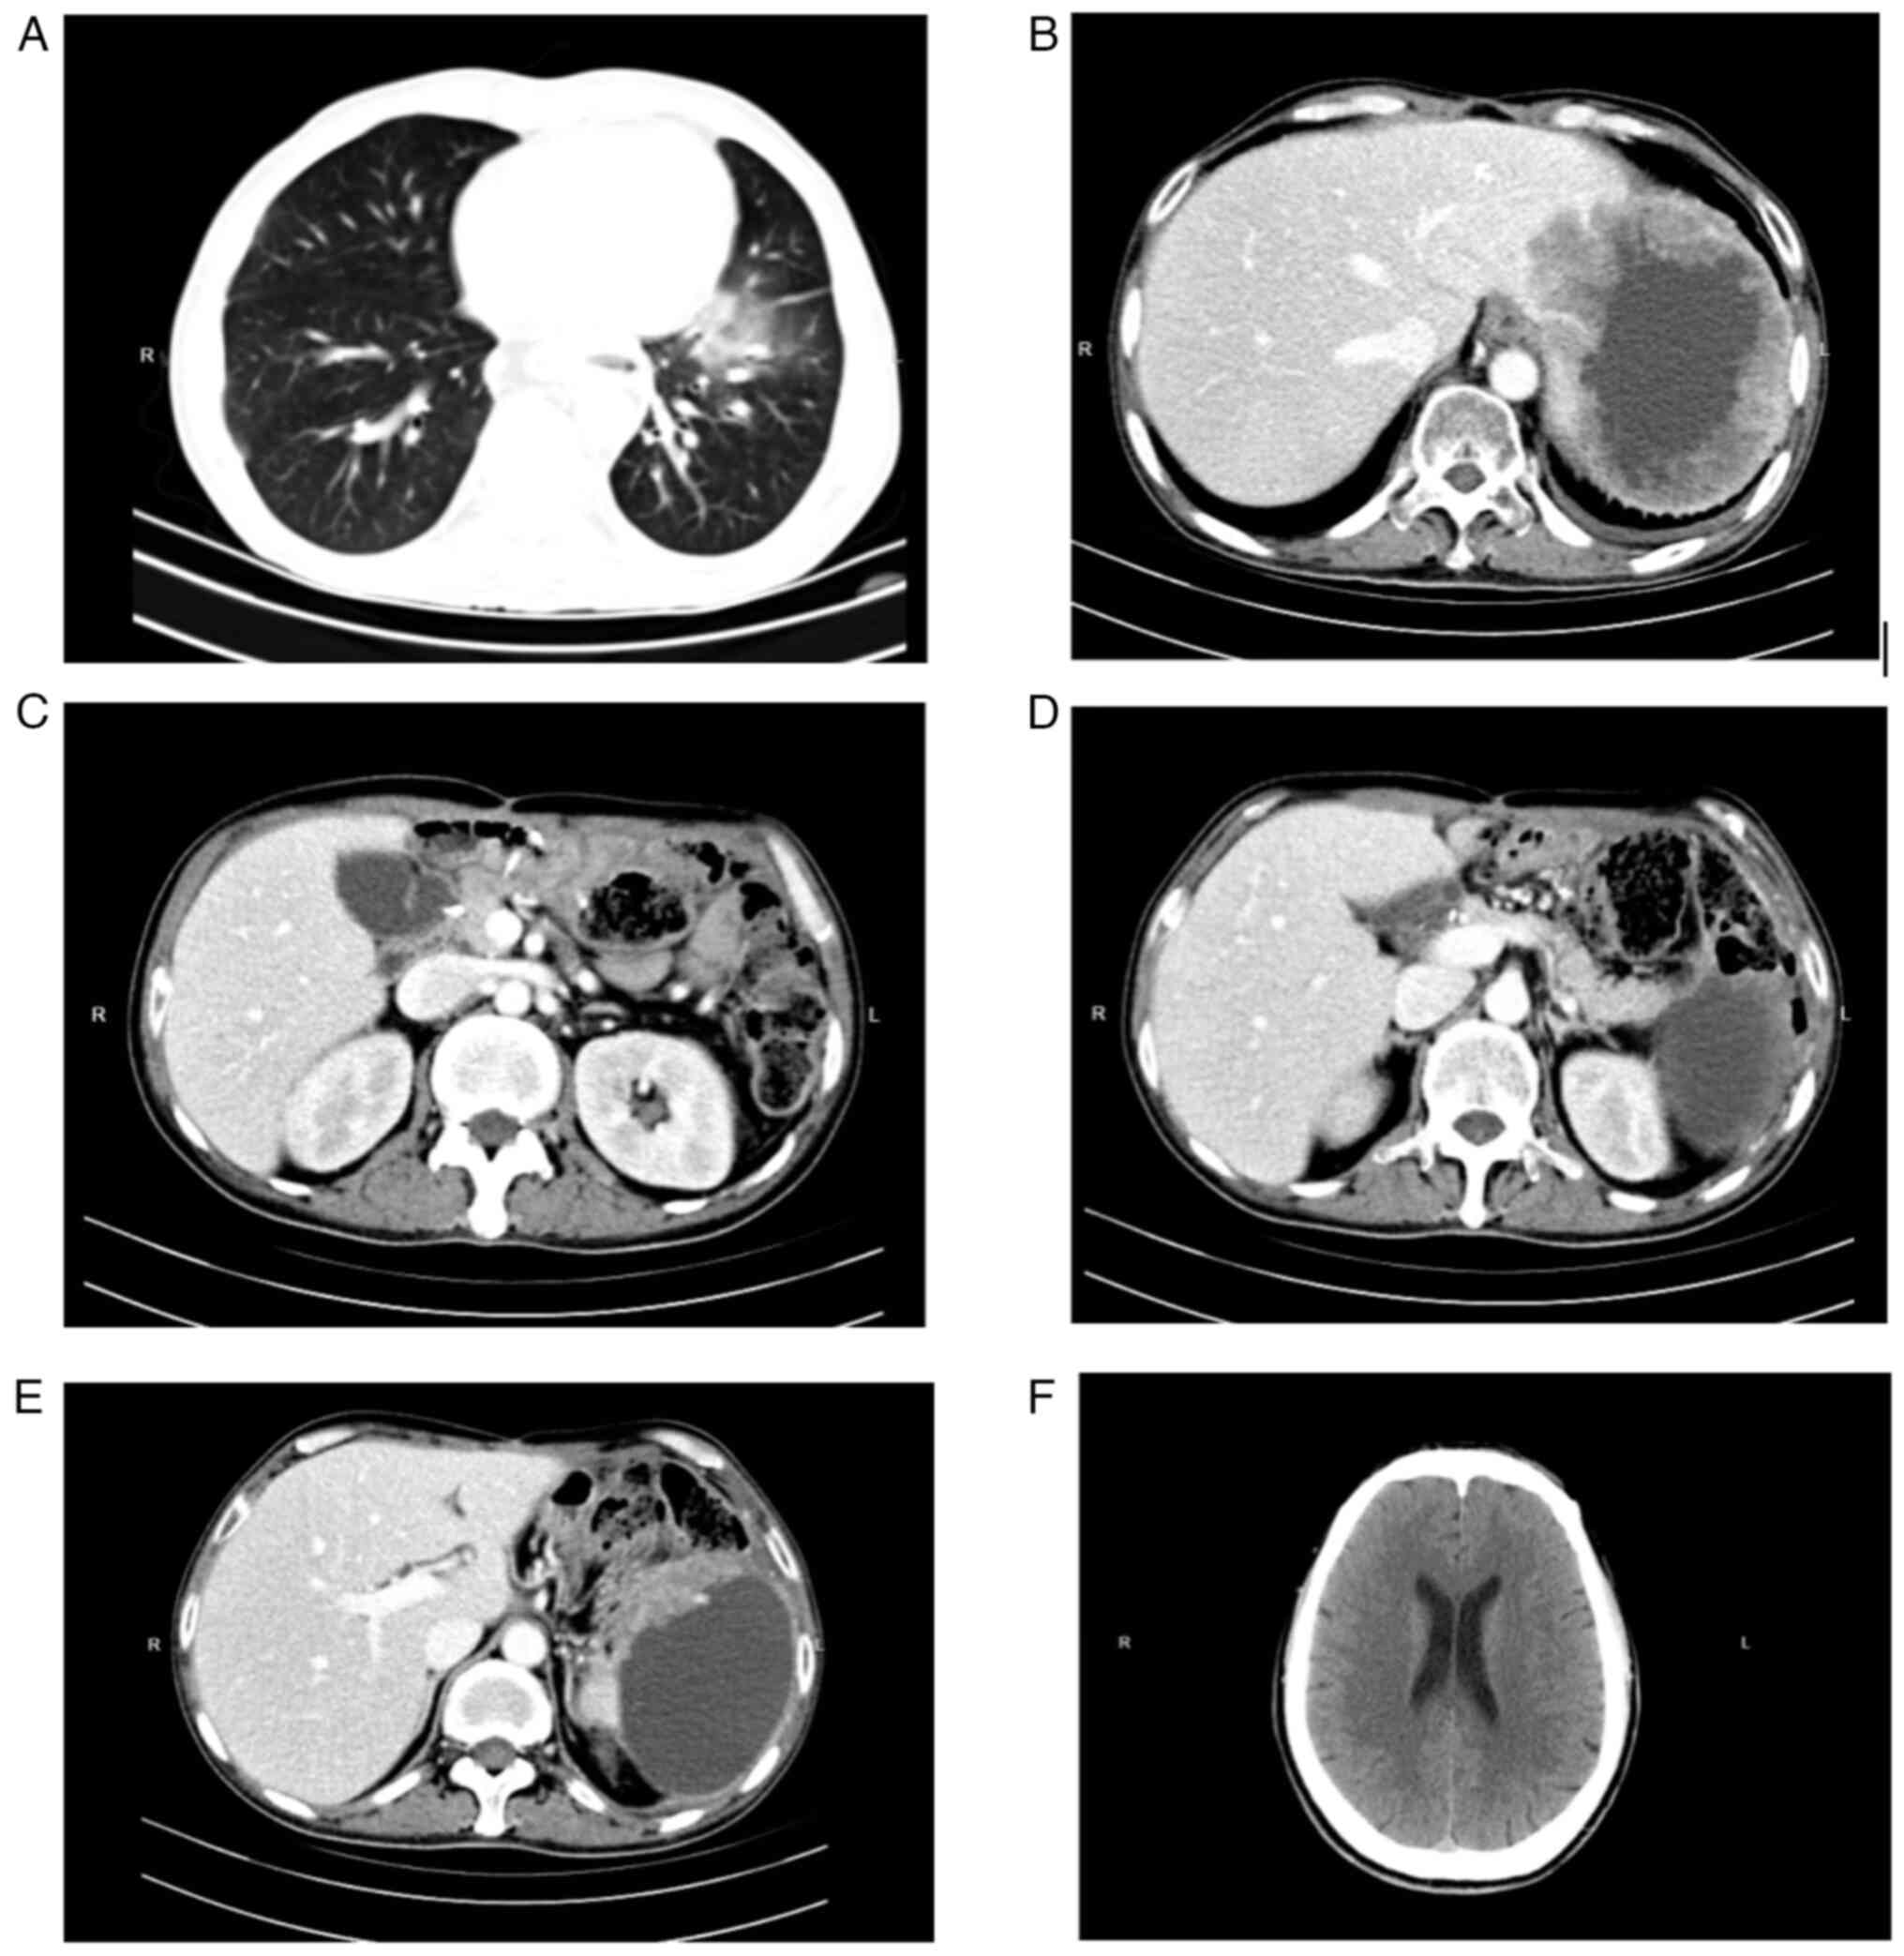

A subsequent computed tomography (CT) scan confirmed the presence of an abdominal mass (Fig. 2). An abdominal plain CT scan detected an irregular soft-tissue mass measuring 125.9×101.3 mm with an irregularly thickened wall in the residual spleen (Fig. 2A). The mass showed uneven enhancement in the arterial phase (Fig. 2B) and no obvious regression in the delayed phase (Fig. 2C). Imaging examinations, such as CT scans (Fig. 3) of the brain, lungs and abdomen, together with US of the liver, gallbladder and pancreas were performed. There were no metastases in the lungs (Fig. 3A), the liver (Fig. 3B), the lymph nodes in the upper abdomen (Fig. 3C), the pancreas (Fig. 3D and E) or the brain (Fig. 3F). A bedside percutaneous splenic mass biopsy was next performed under US guidance (Fig. 4).

Figure 3.

Representative CT scans showing a lack of metastasis. CT scan of (A) the lungs, (B) the liver, (C) the lymph nodes in the upper abdomen, (D) the head of the pancreas, (E) the body of the pancreas and (F) the brain. CT, computed tomography.